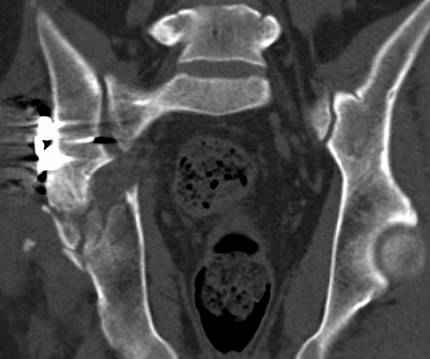

высылаю дополнительно сканы.

итак, второй вариант: высокий двухколонный с вовлечением КПС... Ни одно из основных повреждений не репонировано, кроме задней стенки. Скорее всего попытка реконструкции вертлуги сейчас будет очень травматичной и не очень эфективной, т.е. вероятный риск более значим, чем ожидаемая польза... Лучше подождать, и потом сразу эндопротез

>Вопрос к знатокам: Так что это?

к таковым себя не причисляю, но...обычное дело для нашей страны - выкладывать 3D и не показывать стандартные проекции Judet. Дигност представляет те ракурсы, которые по-его мнению наиболее информативны, более того комп сам достраивает какие-то мелкие повреждения по 3D по своему усмотрению. По данной реконструкции можно предполагать высокий двухколонный перелом с оскольчатыми передней и задней колоннами, оскольчатую высокую переднюю колонну с задним полупоперечником или одно из перечисленных с вовлечение КПС. У меня впечатление за второй вариант, но нужно обследовать нормально - проекции, сканы.